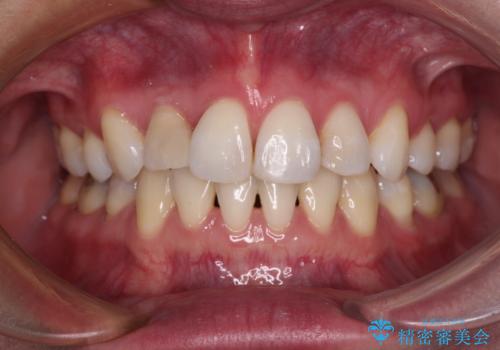

- 八重歯と上の前歯が出っ歯になっていることを気にして来院された患者様です。

横から見た際の口元の飛び出した印象も改善したいとのことで、上下左右の第一小臼歯4本を抜歯し、ワイヤー装置にて抜歯矯正を行うこととしました。

前歯の変色している歯は、神経組織が壊死していたため、矯正治療前に根管治療を実施し、矯正治療後にオールセラミッククラウンにて補綴治療を行うこととしました。

順調に歯が動き、補綴治療も含め2年弱で治療を終えることができました。